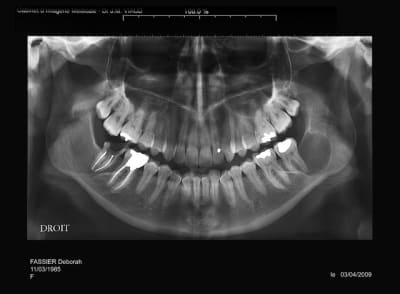

Pano demandé

Ensuite scan

Et pour finir IRM

J’ai commencé par traiter 47 et j'envisageais l'exérèse du kyste mais patiente jeune, jolie et je pense adresser à un stomato qui a plus d'expériences et de doigté

j'ai le scan mais pas ici la corticale linguale est reduite à sa plus simple expression et le kyste remonte sur le trajet du nerf et s'etend aussi en vestibulaire

tu es sur que la 37 n'est pas en cause?

le problème c'est que je n'ai pas revu la patiente pendant 4 ans et que je ne sais pas l'etiologie exacte

je "subis" mon premier problème de dent de sagesse, si j'avais eu à traiter lors du 2° pano ça ne me faisait pas de soucis, mais là!

A priori vu l'évolution sur les radios et l'âge de la patiente je pense qu'il s'agit d'un kératokyste en première intention.

éventullement un améloblastome.

ça peut être également un kyste dentigère laissé en place car il me semble que le kyste est déjà présent sur la première pano et elle est en rapport partiel avec le collet de 38 enclavée mais ça n'est pas caractéristique.